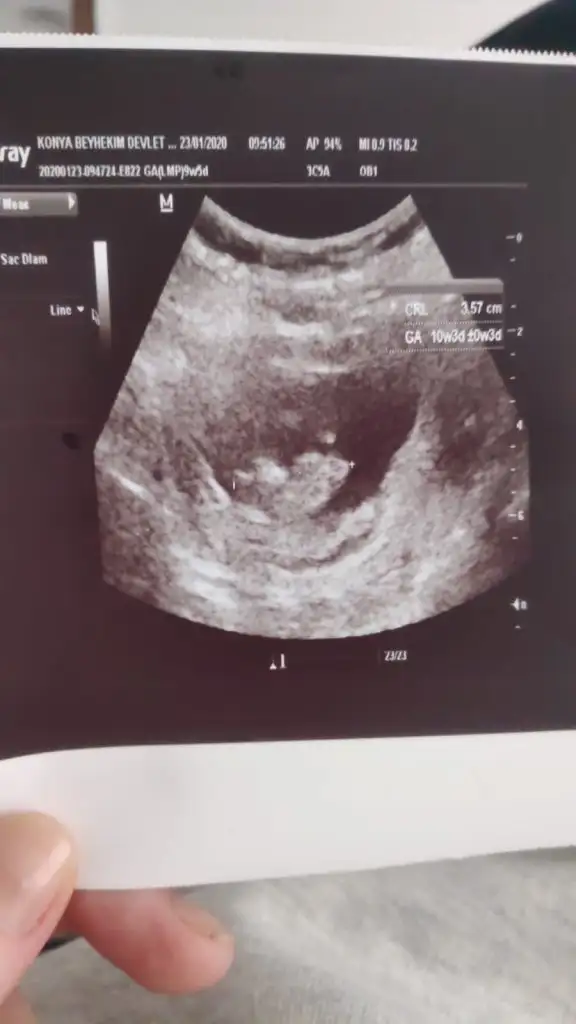

dr soylemeden siz gorun genital nub teorisi ( bebegin cinsiyeti)

Erkek ve kız için 11 yada 12 hafta usg görüntüsü olmalı açıklamalar asagıda yazıyor 😊 rabbim herkesin gönlüne göre nasip etsin inşallah .. ecmain

yabancilarin hepsi biliyor bunu biz neden eksik kalalim gayet bilimsel simdi ellerinde11 12 13 ultrason fotografi olanlar alsin hemen baksin yada koyalim buraya yorumlayalim